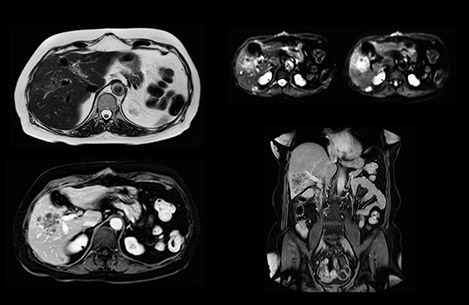

“Our liver exams are quite fast,” says Dr. Baumann. “If the patient tolerates it, we use an arms-up position to reduce the FOV and speed up the exam with dS SENSE.” “We acquire one transversal high resolution T2-weighted sequence with 3 mm slice thickness, for example for pancreas or liver lesions. Then we also add a T2 fat suppressed MultiVane XD SPIR sequence. We perform these two routinely in our liver imaging. We use high dS SENSE factors to significantly shorten scan times to 2-4 minutes, which can improve our protocol; it’s a very robust scan.” “We include mDIXON for the dynamic sequences because of the robust and homogeneous fat suppression we get with that. We had been using eTHRIVE, but we are now quite happy with mDIXON. Sometimes we use a medication to calm the bowels, to further improve the image quality.”

Dr. Baumann then implemented MultiVane XD for motion correction. It uses an extended reconstruction algorithm for imaging that is virtually motion free. “With MultiVane XD we get excellent motion-corrected images with high spatial resolution. We typically first optimize our scan for high image quality, and when satisfied with that, we try to reduce the scan time. So, we combined MultiVane XD with dS SENSE, which allows us to shorten the scan time,” he explains. “The performance of MultiVane XD in liver imaging is outstanding. MultiVane XD with dS SENSE is a powerful development in improving liver image quality.” “As we use breathhold imaging for T2-weighted liver scans, we depend on the patient’s ability to cooperate with the exam. This can present a real challenge when we are looking for small lesions, such as in our oncological patients. However, with MultiVane XD motion correction, we get excellent images. This is important for our surgeons, because they want to know exactly where the lesions are.”